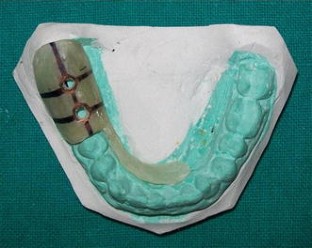

Fig. 2